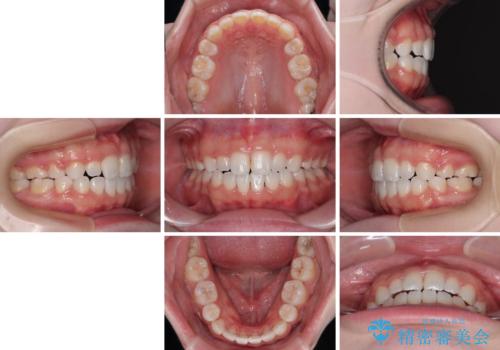

- 前歯が開いて飛び出していることを気にして来院された患者様です。

舌の突出癖により上下前歯は接触できず、更には前方に押し出されて出っ歯になっている状態でした。

当初は舌のトレーニングをしっかりと行ってくださったおかげで、短い期間で治療を終えることができました。